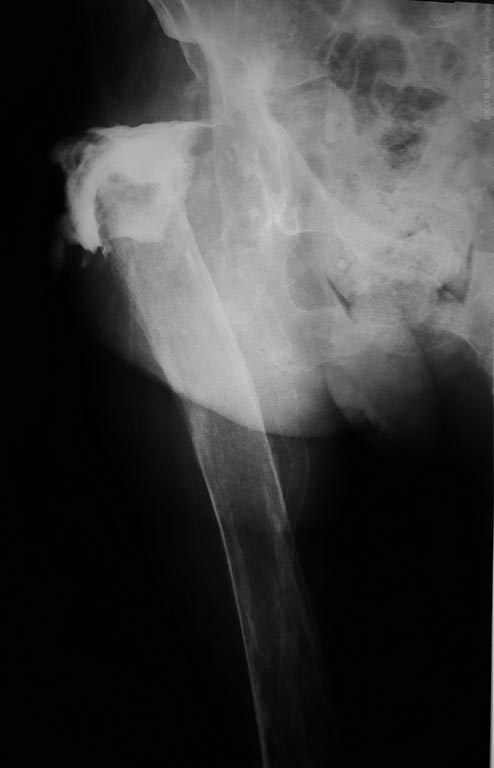

Уважаемые коллеги! Неоднократно обсуждали больную на форуме. Прошу помощи по тактике дальнейшего лечения. Больная, 85 лет, в стацинаре с 7.16г. по поводу:Перипротезной инфекции, удаления эндопротеза тбс в 2014 году, хр.остеомиелита правой бедренной коси и возможно костей таза, свищевая форма. В 09.16 выполнена ревизия свища, санация, удаление остатков цементной мантии из правой бедренной кости. Ведение раны открыто до образования грануляций. в 11.16 выполнена вхо, вторичные швы. Швы сняты через 15 дней. Тогда же диагностирован гнилостно- некротический пролежень крестцовой области. Этпные некрэктомии, абт, периливания крови, плазмы, п/э питание, витамины и т.д., местное лечение, в т.ч. с применениемраневых покрытий, Коллост, асептисорба и др. средств. В настоящее время рана на крестце гранулирует. Планирую свободную кожную пластику. Может несколькими лоскутками. Что икак тут еще придумать не представляю. 3 недели открылся свищ в проекции старого п/ о рубца. В посевах из свища роста нет. Ну и ревизовать снова свищ что то пока не представляю как. Больная намучена. Есть поверхностные пролежни на голенях, левой половине грудной клетки и левом плече. Санируются, заживают. Ввожу после промывания перикисью и физ. р-ром в свищ Бетадин, как зав. гнойнойной хирургии на консилиуме предложила. Только динамики по свищу нет. Там по фистулографии полость у проксимального отдела кости.Стало закрываться отверстие свища, начал турунду с Бетадином ставить, стал экссудат скапливаться. Но полость то там видимо остается. После введения перикиси выходят ошметки клетчатки из раны. Уже мысльможет попробовать смешать Литар с антибиотиком, нум.б. ванко-, ввести в полость и зашить наружное отверстие свища? Пока не решаюсь, не знаю. Больная измучена, хотя и активизируем ее в пределах кровати и даже стоит с инструктором и в ходунках шаги делает. Может еще что то можно сделать со свищем. Может другие препараты? Сейчас анемия 81г/л, гипопротеинемия: общ. белок 63. лейкоцитоз 13, в динамике уменьшился , срб: 92. яФункционирующая эпицистостома. На днях переставили фолея- забился. В посеве мочи отмечен рост м/ф в диагностическом титре. Анализ в работе. Что делать дальше больной? Пересадить кожу, отсанироаать каким то образом свищ? Каким? Спасибо за конкретные предложения.